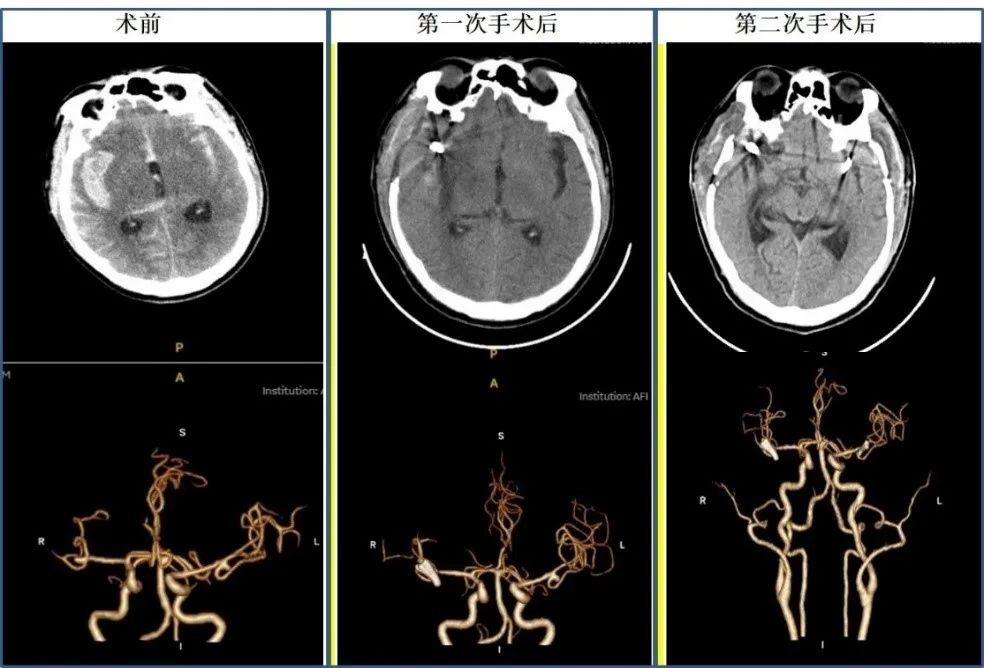

结合患者病情及影像学表现,丰育功主任、郭品副主任决定采用分期手术方案,先行处理动脉瘤,实施“右侧动脉瘤夹闭术+去骨瓣减压术”,患者10天后康复出院。2个月后,刘先生再次到青大附院接受了“左侧大脑中动脉瘤夹闭术+右侧颅骨修补术”,术后身体状况恢复良好。